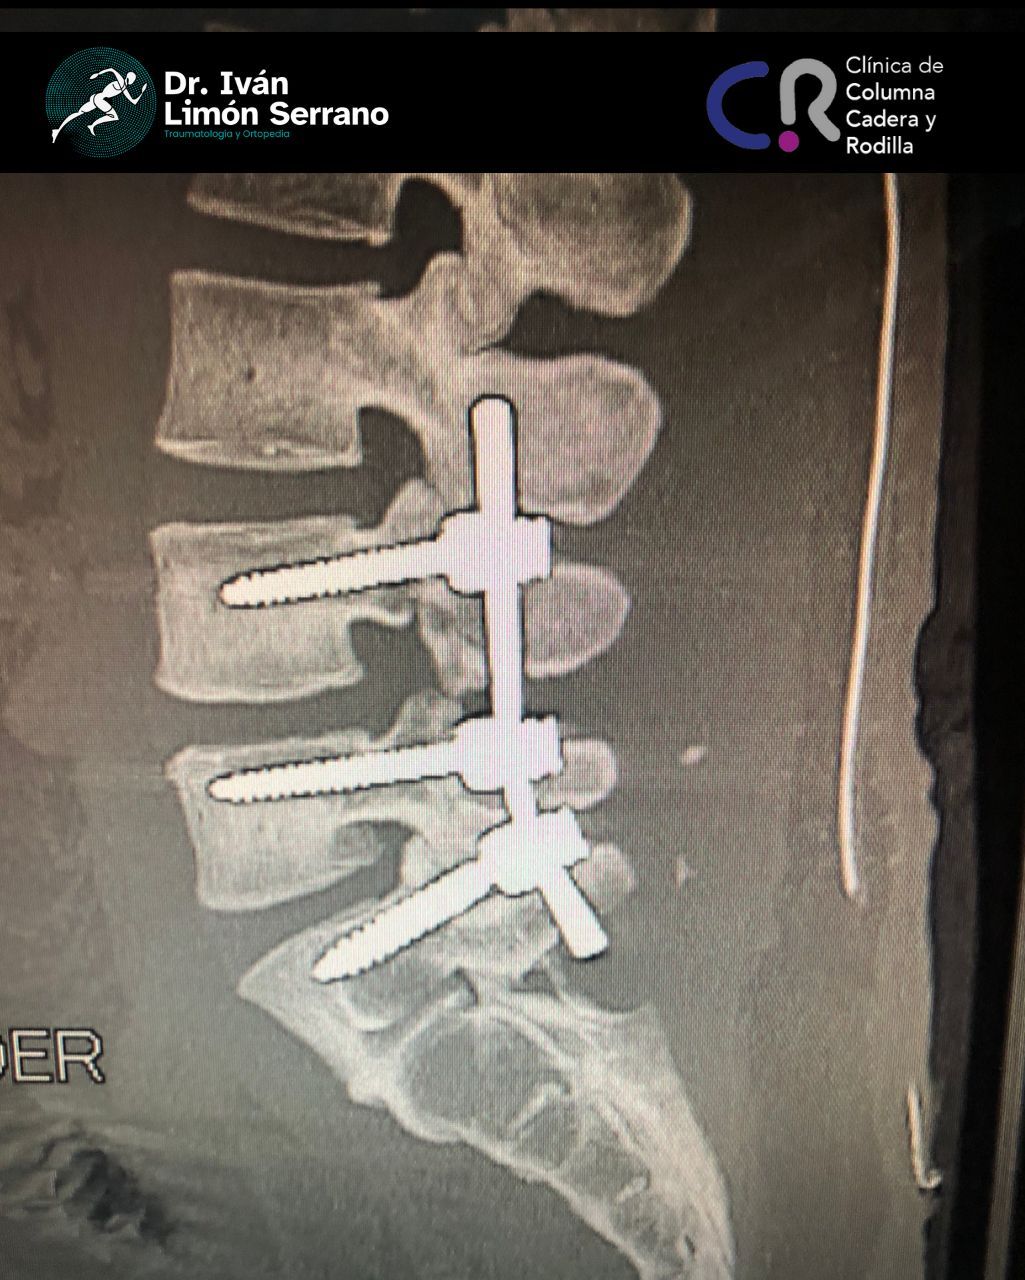

• Cirugía de columna

• Cirugía columna